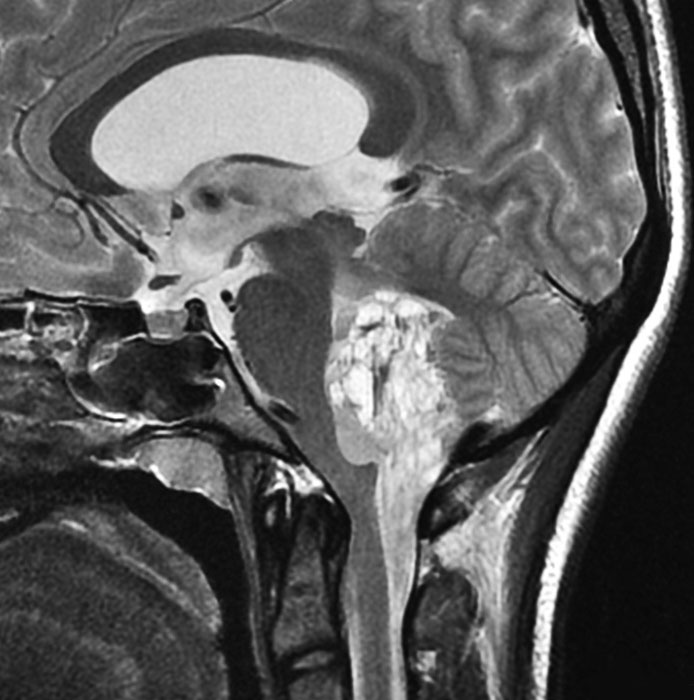

第4脳室床に発生した典型的な上衣腫 EPN-PFA の画像です。水頭症になって,頭痛と嘔吐,意識障害で発症しました。典型的なMRI画像と病理所見です。MRIでは第4脳室からマジャンディー孔を越えて脊髄背側まで長く腫瘍が伸びています。腫瘍内部に小さなのう胞が複数みられます。病理像では,血管周囲に細胞核がない無核野が認められます。血管周囲に伸びた繊細な単極性突起が集まった領域です。これは,血管周囲偽ロゼット perivascular pseudorosette という上衣腫に特徴的な病理所見です。

幼児の巨大な上衣腫です。左ルシュカ孔から延髄を取り囲む様に小脳延髄角槽に進展しています。最も典型的で治療が難しいタイプです。これはT2強調画像ですが,ガドリニウム増強されないものでした。

左が術前,右が術後です。脳底動脈の周囲が摘出できませんでした。幼児ですが手術後には局所照射をするしか方法がありません。

病理組織診断では退形成性上衣腫,MIB-1は40%以上にも達します。

この様なEPN-PFAは,脳外科の先生と小児科の先生が最も苦労するものですが,予後は極めて不良です。